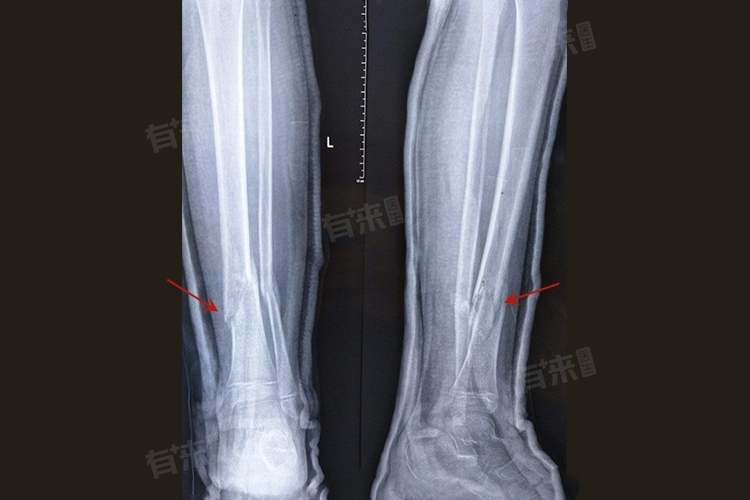

骨不连即骨折后骨头未能如期愈合,导致骨折部位长时间无法连接在一起,是一种骨折后愈合不良的病理状态。当骨折端无法有效连接时,患者会经历一系列的症状,如持续性疼痛、功能障碍等。

4、结构变形:长期的骨不连可能导致骨折部位的解剖结构逐渐变形,可能表现为骨折部位的弯曲、缩短或旋转等畸形。